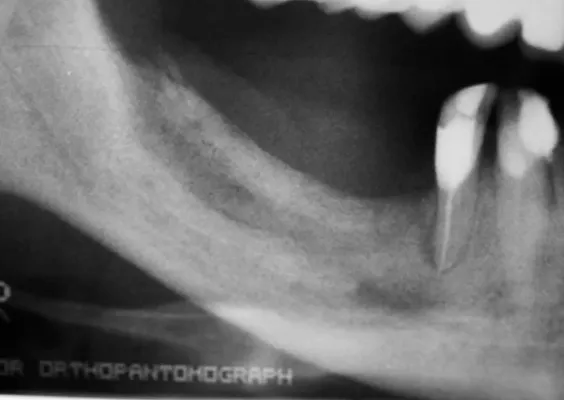

Odbudowa kostna w ODCINKACH BOCZNYCH SZCZĘK - PODNIESIENIE DNA ZATOKI SZCZĘKOWEJ (SINUS LIFT)

Technika odbudowy kostnej stosowana w celu wszczepienia implantów w zanikłe, boczne odcinki szczęk. Najistotniejszą przyczyną utraty kości wyrostka zębodołowego szczęk w odcinkach bocznych są ekstrakcje zębów. Niedostatek kości w wymiarze pionowym stanowi szczególną anatomiczną przeszkodę dla implantacji w okolicy dna zatoki szczękowej. Chcąc odbudować uzębienie i przywrócić funkcję żucia, trzeba podjąć wieloetapowe leczenie rekonstrukcyjne.

Zabiegiem, który rozwiązuje ten problem, jestpodniesienie dna zatoki szczękowej (sinus lift), czyli odbudowa kostna w okolicy zębów trzonowych. Ubytek kości uzupełniany jest materiałem kościotwórczym, który układany jest pod błoną wyścielającą zatokę szczękową, zwaną membraną Schneidera. Zmniejszając objętość zatoki szczękowej, tworzy się tym samym stabilną strukturę kostną, umożliwiającą zabieg implantacji wszczepów śródkostnych.